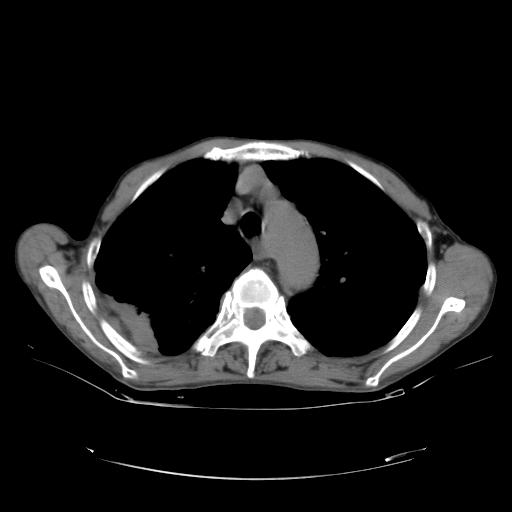

女,72岁,咳嗽一周余,突发右下肢无力二天。

来院做头颅+胸部ct平扫

遂加作增强:

胸部病变平扫35hu,增强强化至70hu

这个病人首先是胸部病变的定位到底是肺内还是肺外。仔细观察块影位于胸膜下,与胸膜间有透亮带,且近端血管未见明显推移而是引流样改变,形态分叶,说明这个病灶位于肺内胸膜下。很可能是腺癌,腺癌最易致颅内高密度转移灶。局部胸膜有侵犯。

本例颅内见多发大小不等高密度灶,有强化及水肿;另外,胸锁关节层面可能是第四胸椎及右侧肋骨起始部骨质欠连续,椎旁软组织肿胀,建议调骨窗观察。

诊断:右下肺癌伴颅内、胸椎、肋骨转移可能性最大。

右肺周围型肺癌并脑转移,肺气肿.肺大泡。